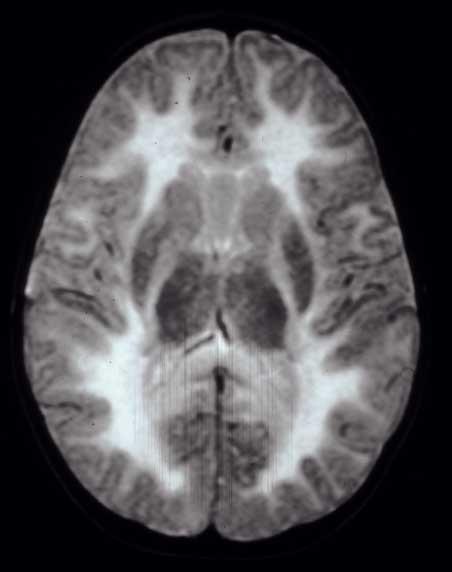

Canavan Disease Canavan Disease

• Diffuse, subcortical WM + globi pallidi / thalami (not putamina) Diffuse, subcortical WM + globi pallidi / thalami (not putamina)

• Spectroscopy: High NAA peak (diagnostic!) Spectroscopy: High NAA peak (diagnostic!)

• Mnemonic: Ca Mnemonic: CaNAANAAvan van